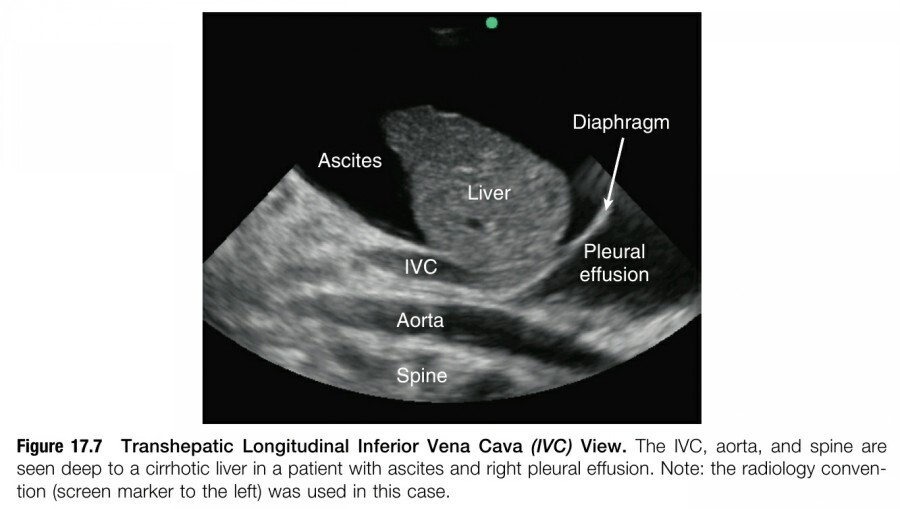

Liver parenchyma는 IVC를 보는데 있어서 매우 뛰어난 acoustic window를 제공하므로, subcostal IVC view를 얻을 수 없을 때(eg, pregnancy, postoperative wounds, dressing, bowel gas, patient discomfort) 유용하다. Transducer를 mid-axillary line에 대고 transducer orientation marker를 cephalad 쪽으로 향한다. Transducer를 posterior 쪽으로 tilting 하면(ie, ultrasound beam을 posterior 쪽으로 향하면) liver와 diaphragm을 지나는 IVC의 long-axis view를 capture 할 수 있다. Aorta는 이 vewi에서 IVC 보다 더 깊은 곳에 위치한다(figure 17.6, 17.7).